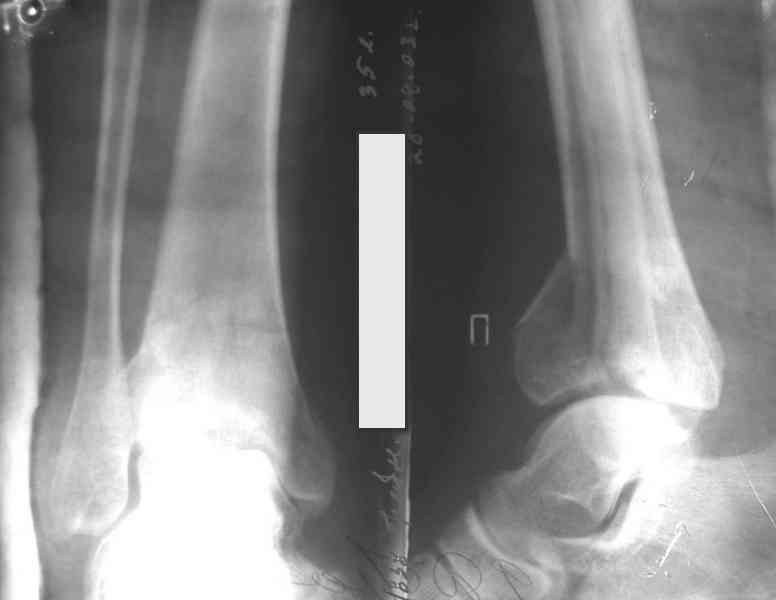

Это типичный перелом пилона, который надп лечить только открыто.Извини те что опоздал к обсуждению, но даже если вы уже оперировали больного по Илизарову это даже лучше.Посылаю картинки.

На рентгенограммах типичный перелом пилона по типу С-3. есть опыт до 100 открытых опреаций у нас в клинике. 20 примерно в год. Принцип один -все внутрисуставные переломы нуждаются в открытой репозиции и внутренней стабильной фиксации. При поступлении КТ не надо, так как получается только нагромождение костей. Истинной картины нет. Главное восстановить длину малоберцовой кости - это ключ к успеху. При поступлении меньше всего надо думать о сосудистых расстройствах, т.к. сама операция и репозиция даже сначала частичная даёт улучшение сосудитых нарушений. Причём очень быстро. Операция в 2этапа. При поступлении доступ позади наружной лодыжки, причём обязательно. После этого репозиция малоберцовой кости и фиксация пластиной 1/3 трубки под винт 3,5. Дренаж и любой аппарат наружной фиксации. Затем после спадения отёка на 5-7-10 день аппрат снимается и дугообразный разрез спереди от медиальной лодыжки 10-12 см. Главной чтобы расстояние между 1 и вторым разрезом было не меньше 7-8 см. Тогда не будет некрозов лоскутов. Таранная кость используется как матрица на неё укладываются отломки и фиксируются пицами. Ренг-контроль. Отломки лежат все отдельно, но ничего не высыпется. При переломах С-3 всегда нужна костная пластика (из крыла). Фиксация пластиной лист клевера простой или LCP. Гипс не нужен. Дренаж до 48 часов. Операция длится 3-4 часа обязательно без жгута. Посылаю примерно такой же случай.